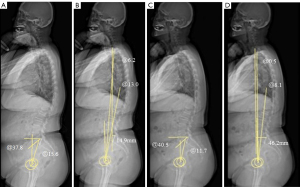

Measurement of spino-pelvic sagittal parameters

In EOS lateral images, multiple spino-pelvic sagittal parameters were measured, including pelvic incidence (PI), PT, SS, thoracic kyphosis (TK), LL, sagittal vertical axis (SVA), spino-sacral angle (SSA), T1 spinopelvic inclination (T1SPI), and T9 spinopelvic inclination (T9SPI) before and after TKA (Figure 1A-1D). PI was defined as the angle between the line from the center of the femoral heads to the midpoint of the upper endplate of S1 and the perpendicular line from the midpoint of the S1 upper endplate (normal =45±15°). If the femoral heads were not overlapping, the midpoint of the line connecting the centers of the femoral heads was taken (6). SS was the angle between the upper endplate of S1 and the horizontal line (normal =37.7°±9.7°) (Figure 1A) (6). PT was the angle between the line from the center of the femoral heads to the midpoint of the upper endplate of S1 and the vertical axis through the center of the femoral heads (normal =12.6°±4.5°). If the femoral heads were not overlapping, the midpoint of the line connecting the centers of the femoral heads was taken (Figure 1A) (6). TK is measured as the angle between the upper endplate of T1 and the lower endplate of T12, with normal values ranging from 20 to 40 degrees. LL is defined by the angle between the upper endplate of L1 and the upper endplate of S1, typically averaging 54.6 degrees with a standard deviation of ±10 degrees (6). The SVA represents the horizontal distance between the plumb line passing through the center of C7 and the posterior superior corner of the S1 upper endplate. If the plumb line is anterior to the posterior edge of S1, it is recorded as a positive value (+), with a normal value being less than 5 cm (6,7).

T1SPI/T9SPI is the angle between the line from the center of T1 or T9 to the center of the femoral heads and the vertical axis through the center of the femoral heads. If the femoral heads do not overlap, the midpoint of the line connecting their centers is used. If the line from the center of T1 or T9 to the center of the femoral head is anterior to the vertical axis, the angle is recorded as a negative value (−) (20).

SSA is the angle formed by the line from the center of C7 to the midpoint of the upper endplate of S1 and the S1 upper endplate, with normal values around 133±8 degrees (9). The differences between preoperative and postoperative values of these parameters are calculated and represented as delta (Δ), for example, ΔSSA = pre-SSA − post-SSA.